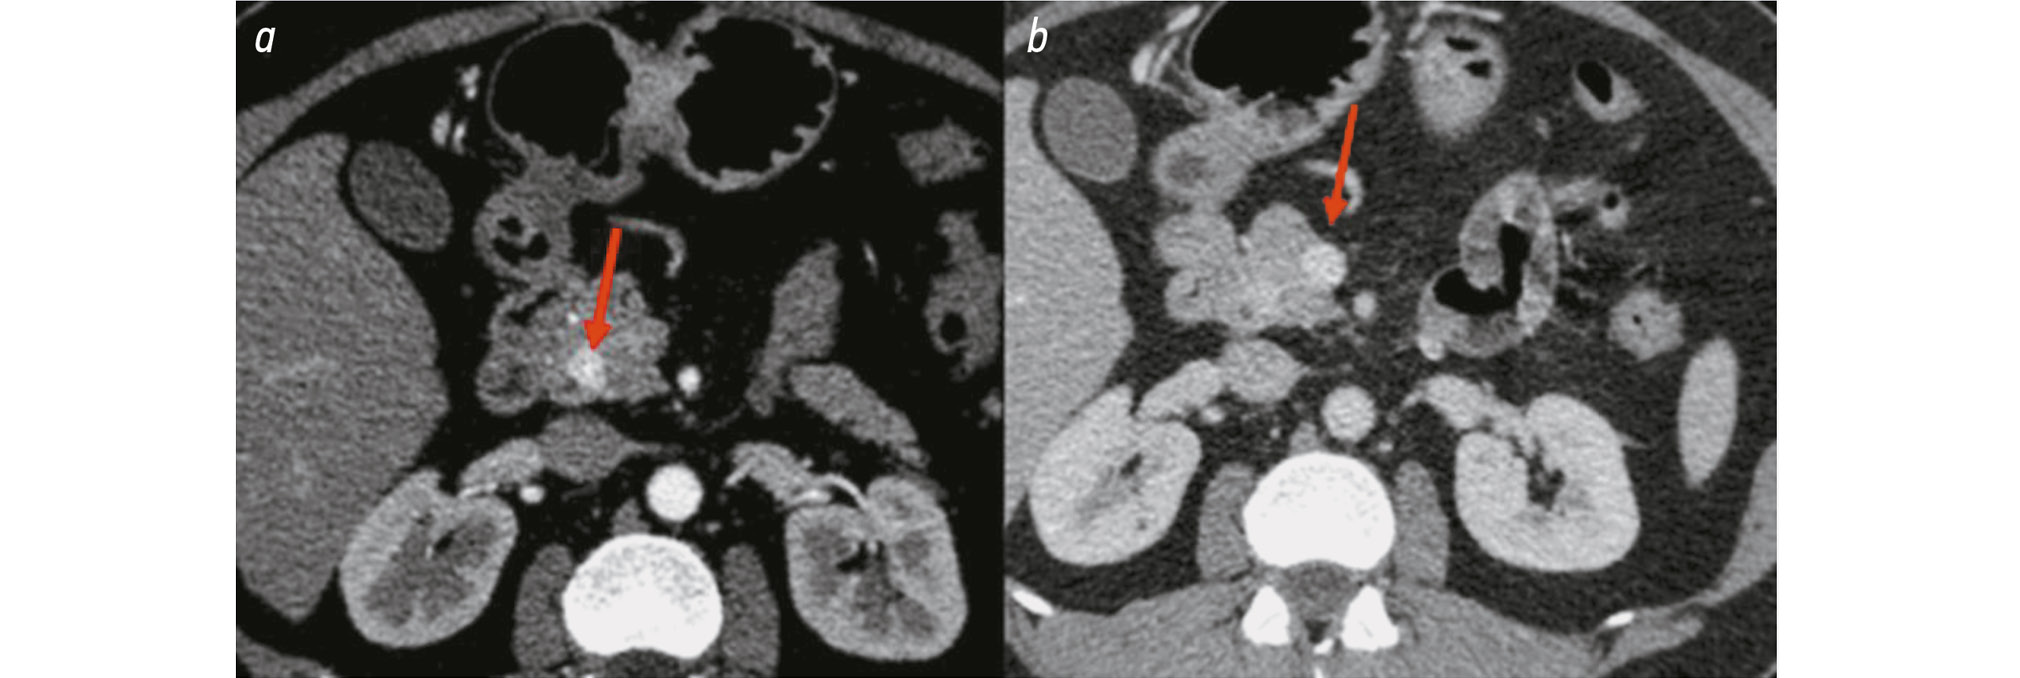

As with pancreatic NETs, gastric NETs can also show variable contrast enhancement. Fig. 4 illustrates a NET located in the upper wall of the gastric cardia, which displayed increased enhancement during the venous phase and minimal enhancement during the arterial phase.

Fig. 4. Gastric neuroendocrine tumor: a, low contrast uptake by tumor tissue, arterial phase; b, a hyperintense lesion in the upper wall of the gastric cardia (up to 6 mm), venous phase.